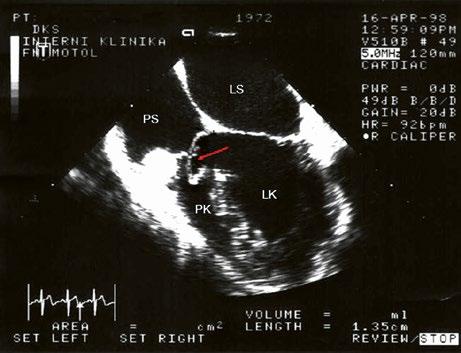

Obr. 45.31 Spontánní uzávěr velkého defektu komorového septa septálním cípem a závěsným aparátem trikuspidální chlopně (šipka), bez reziduálního zkratu, TEE

LK – levá komora, LS – levá síň, PK – pravá komora, PS – pravá síň